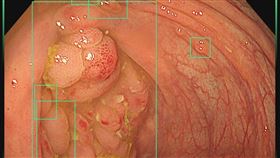

「1類息肉」潛伏20年!他拖6月慘變大腸癌

照大腸鏡時發現有息肉很正常,即時切除就能減少罹大腸癌...

大腸息肉不是切了就OK!「5情況」恐癌變

大腸癌是國人僅次於肺癌的新發癌症,醫師黃軒表示,一般...